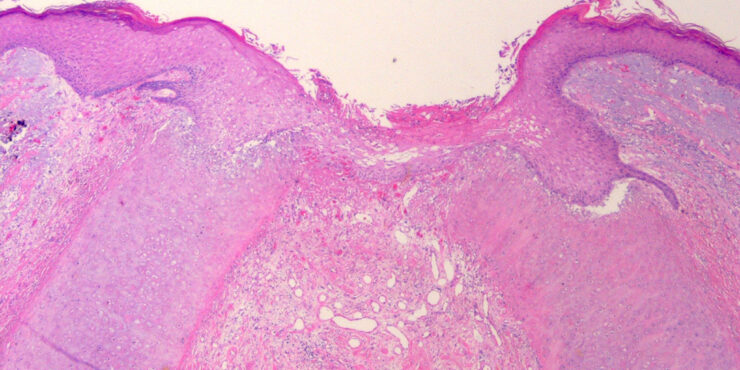

Read MoreColloid milium =الدخنية الغروانية OLYMPUS DIGITAL CAMERA OLYMPUS DIGITAL CAMERA Colloid Milium Colloid milium is a rare condition characterized by (1) the presence of multiple, dome-shaped, amber- or flesh-colored papules developing on light-exposed skin and (2) the observance of dermal colloid under light microscopy. The 4 variants are (1) an adult-onset type, (2) a nodular […]